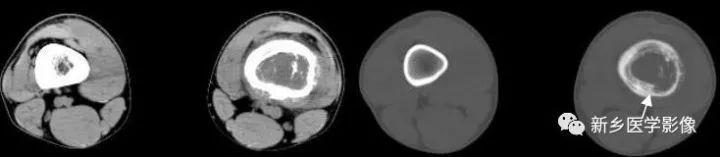

图7-18 骨膜增生CT图像

软组织窗(a)和骨窗(b)显示左侧股骨下段骨皮质破坏,髓腔扩大,后外侧骨膜增生(↑)。